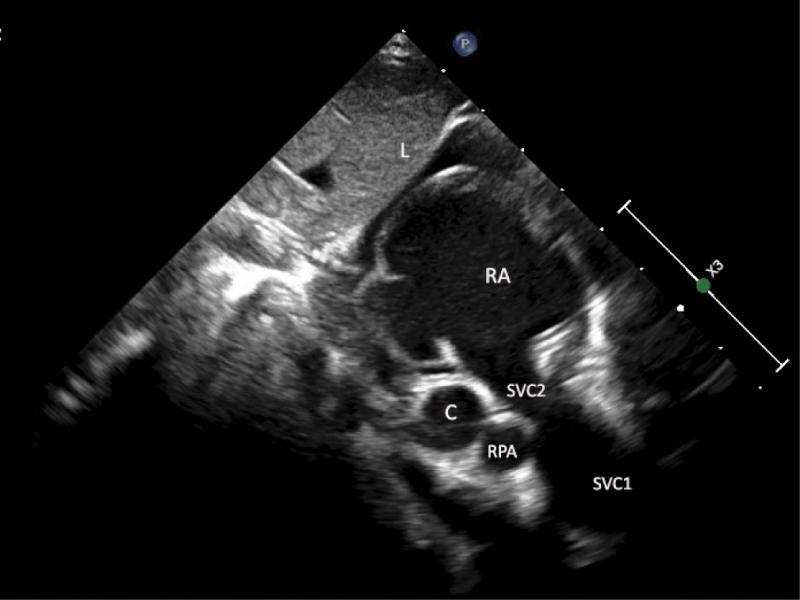

A supracardiac type of total anomalous pulmonary venous drainage (TAPVD) through a 12-millimeter-wide vertical vein with significantly dilated brachiocephalic vein and even more enlarged superior vena cava was diagnosed based on echocardiography (Fig. 1, Fig. 2, Fig. 3, Fig. 4, Fig. 5), and confirmed using CT angiography (Fig. 6, Fig. 7, Fig. 8). A 10 mm secundum atrial septal defect permitted a relatively unrestricted right-to-left atrial flow, and thus the survival of the patient. The right atrium and right ventricle were also enlarged. Echocardiographic signs of pulmonary hypertension were present. The marked dilatation of the SVC and unusual, turbulent flow pattern within this vessel, which was detected on ECHO, suggested that the right upper pulmonary vein drained separately to the SVC. This suspicion was not confirmed by either CT angiography or direct surgical inspection.

Subcostal sagittal view showing the entrance of the SVC (SVC2) to the right atrium (RA) and the interatrial septum. The diameter of the proximal part of the SVC seems normal; however, its more distal part is markedly dilated (SVC1). The valve of the foramen ovale is shifted toward the left atrium. Also visible are: transverse section of the right pulmonary artery (RPA) and the pulmonary veins’ confluence (C). The layer of the fluid in the pericardial space is suggestive of heart failure